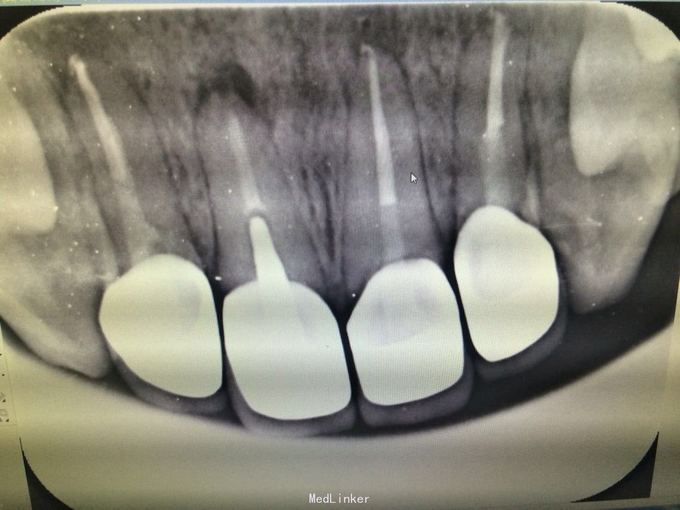

11 12 21 22金属烤瓷冠修复,牙龈发黑,冠颈部牙龈萎缩红肿有黑褐色腐质物,探出血,叩(-).23近中颊侧扭转倾斜.36 37 46 47残根,松动轻,全口牙结石中度,牙齿颜色偏黄,全景片示,11 12 21 22根管治疗不完善,根尖低密度影,有金属桩修复

11 12 21 22死髓牙,不良修复体,牙龈炎 36 37 46 47残根 牙列不齐 处置:全口洁治。 比色,拍照,取模型做蜡型。 拆除旧修复体,拆桩核,做根管治疗,纤维桩修复,牙体预备,取模,做临时冠,粘固。11 12 21 22全瓷冠修复,13 14 23 24 31 32 33 34 41 42 43 44瓷贴面修复。